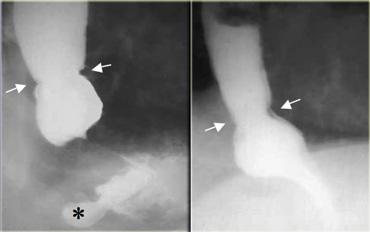

Bên trái là hình ảnh bệnh nhân có vòng thực quản do co thắt cơ.

Lưu ý túi thừa dạ dày phát hiện tình cờ (dấu hoa thị).

Vòng A thực quản do co thắt cơ. Hình ảnh thay đổi trong quá trình thăm khám và có thể không tồn tại liên tục.

Bên trái là hình ảnh một bệnh nhân khác với vòng thực quản không tồn tại liên tục tại đỉnh của thoát vị hoành trượt.

Vòng B thực quản nằm tại ranh giới biểu mô vảy-trụ, còn được gọi là đường ‘Z’.

Hình ảnh không thay đổi trong suốt quá trình thăm khám.

Bên trái là hình ảnh bệnh nhân có vòng ‘B’ (các mũi tên) nằm cách cơ hoành vài cm, tại đỉnh của thoát vị hoành trượt.

Lưu ý hình ảnh không thay đổi trên hai ảnh này.

Bên trái là hình ảnh nam bệnh nhân 52 tuổi với triệu chứng nuốt khó từng đợt.

Hình ảnh ngoài cùng bên trái không cho thấy bất thường, tuy nhiên thực quản đoạn xa chưa giãn căng.

Khi thực quản đoạn xa giãn căng, vòng B Schatzki rộng 13 mm (các mũi tên) gây tắc nghẽn từng đợt được hiển thị rõ tại đỉnh của thoát vị hoành (đầu mũi tên).

Bên trái là hình ảnh nam bệnh nhân 71 tuổi với triệu chứng đau ngực sau bữa ăn nhanh.

Khiếm khuyết ngấm thuốc gây tắc nghẽn ở đoạn xa (mũi tên) là một mảnh thịt đã di chuyển vào dạ dày trong quá trình thăm khám.

Hình ảnh thực quản chụp theo dõi cho thấy vòng B Schatzki (các mũi tên) là nguyên nhân gây tắc nghẽn.